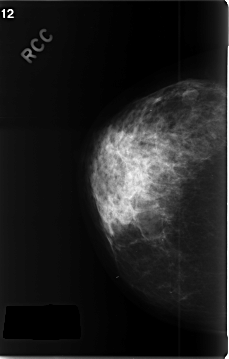

C_0343_1.RIGHT_CC

RIGHT_CC LINES 4656 PIXELS_PER_LINE 2968 BITS_PER_PIXEL 12 RESOLUTION 50 NON_OVERLAY

FILE: C_0343_1.LEFT_CC.OVERLAY

TOTAL_ABNORMALITIES 1

ABNORMALITY 1

LESION_TYPE MASS SHAPE OVAL MARGINS ILL_DEFINED

ASSESSMENT 5

SUBTLETY 5

PATHOLOGY MALIGNANT

TOTAL_OUTLINES 1

BOUNDARY